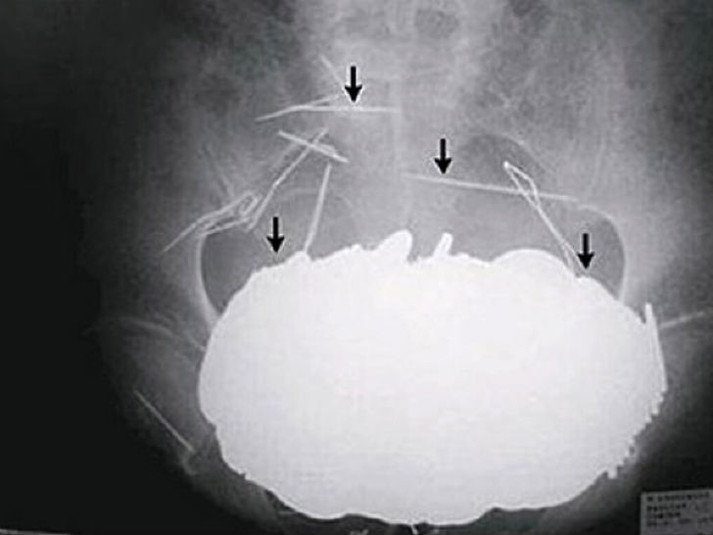

Вот буквально несколько примеров тех вещей, которые были обнаружены в человеческом желудке.